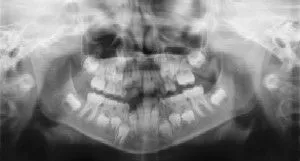

Dental Radiographs (X-Rays)

Radiographs are a vital and necessary part of your child’s dental diagnostic process. Without them, certain dental conditions can be missed. Radiographs allow dentists to diagnose and treat health concerns that cannot be detected during a clinical examination and they detect much more than cavities. For example, radiographs may be needed to survey erupting teeth, diagnose bone diseases, evaluate the results of an injury, or plan orthodontic treatment. If dental problems are found and treated early, dental care is more comfortable for your child and more affordable.

The American Academy of Pediatric Dentistry recommends radiographs every six months for children with a high risk of tooth decay. Approximately every 3 years, it is a good idea to obtain a complete set of radiographs which can include a panoramic with bitewings and periapicals.

Pediatric Dentists are particularly careful to minimize the exposure of their patients to radiation. With contemporary safeguards, the amount of radiation received in a dental x-ray examination is extremely small. The risk is negligible. In fact, dental radiographs represent a far smaller risk than an undetected and untreated dental problem. Today’s equipment filters out unnecessary x-rays and restricts the x-ray beam to the areas of interest. High-speed film and proper shielding assure that your child receives a minimal amount of radiation exposure.